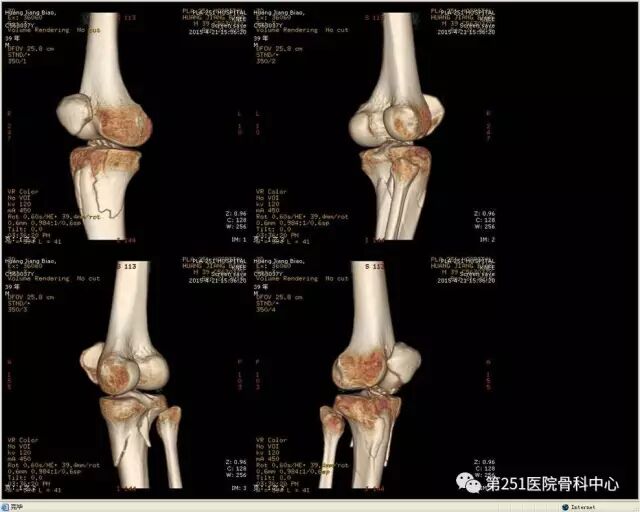

病例6:男性,39岁,车祸伤SchatzkerⅥ型胫骨平台骨折。

![]()